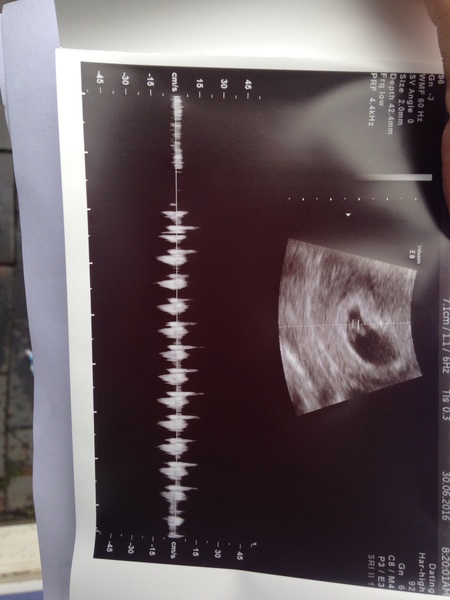

Evergreen17 · 30/06/2016 09:13

In tears GrinGrinGrinGrinGrin

A 9 mm bean with a heart beat like a train Smile

Ah, awesome pic Ever! Great news.